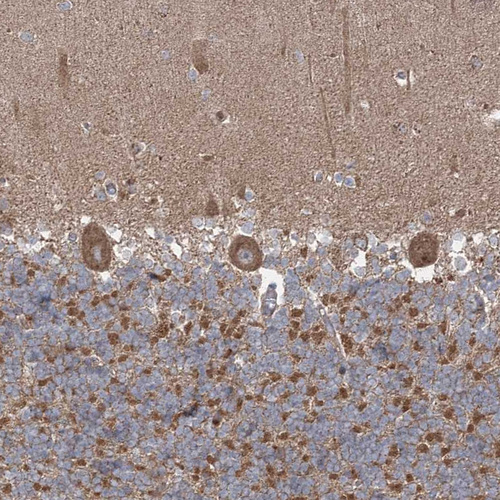

Immunohistochemical staining of human cerebellum, gastrointestinal, kidney and skeletal muscle using Anti-LRPPRC antibody HPA036408 (A) shows similar protein distribution across tissues to independent antibody HPA036409 (B).